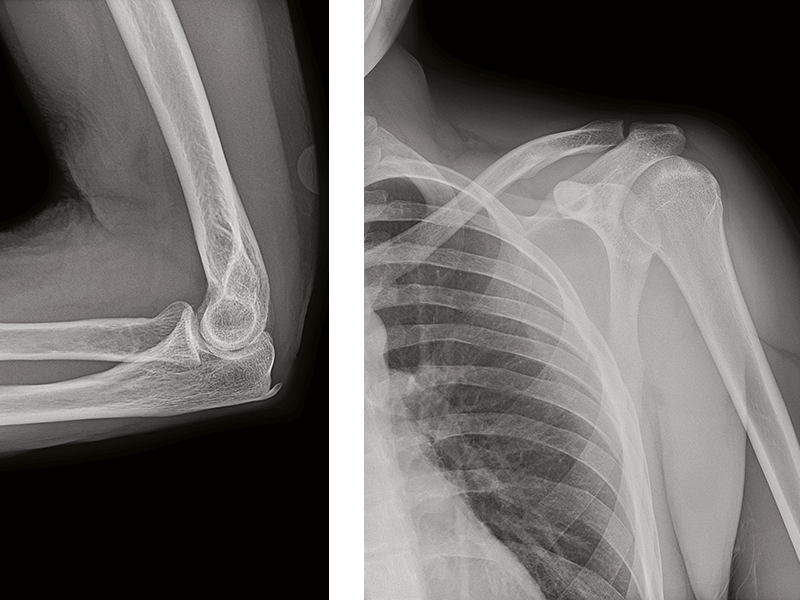

Extraordinary anatomical detail at low dose in every X-ray image.

Helix advanced image processing algorithms harness the full high-resolution power and exceptional dose efficiency of FlashPad HD detectors to deliver outstanding clarity and extraordinary anatomical detail where it matters most.

Anatomy specific image enhancement

Clear bone and soft tissue presentation across different anatomies and views.